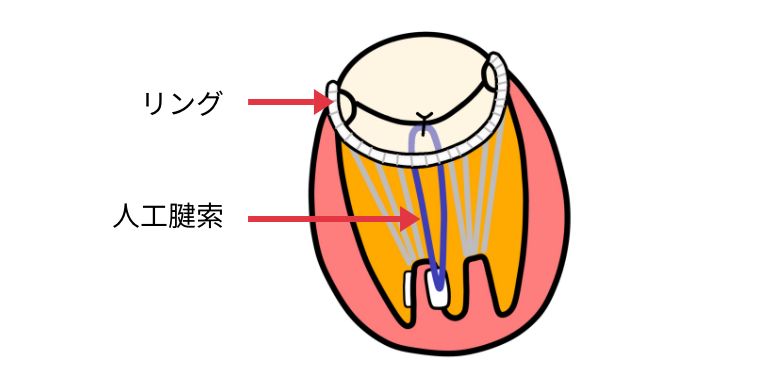

大動脈瘤は、偶発的に診断されることが多いですが、一定のサイズを超えると破裂する可能性があり、破裂をきたした場合の死亡率は80%以上とされ、破裂前の治療が大事になります。治療法は、人工血管置換術とステントグラフト内挿術があります。

併存疾患や年齢により人工血管置換術に耐えれない方に向けて、体への負担が少ない治療が開発されました。

足の付け根の血管から、カテーテルを使用して人工血管(ステントグラフト)を大動脈に挿入し、大動脈瘤破裂を防ぐ治療になります。

当院では皮膚を切開しないで行うステントグラフト治療を積極的に施行しております。他施設に先駆けて2013年から皮膚を切開しないでステントグラフト治療を行い、胸部大動脈瘤でも導入しております。導入から500例を超える症例に皮膚を切開しないステントグラフト治療を行いましたが、入院日数は平均3-6日です。局所麻酔で行うため、全身麻酔が困難といわれた方に対しても安全に治療をしています。

腹部大動脈瘤破裂に対して施行した緊急ステントグラフト内挿術

胸部大動脈瘤に対して施行したステントグラフト内挿術